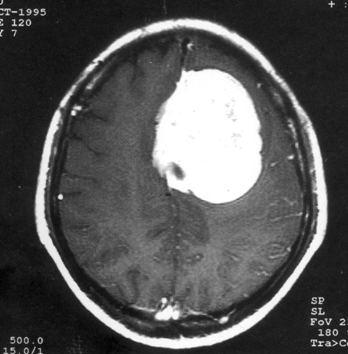

问题 病历摘要:??患者,男,40岁。发作性左下肢抽搐1年余,每次发作3~5分,每周发作1~2次。每次发作后感左下肢乏力,约半日后可自行恢复。既往身体健康。体检:神清,头顶部偏右有局限性骨性隆起(1.5×1.5cm),左鼻唇沟稍浅,伸舌居中。感觉、运动无明显异常。左浅反射减退,左下肢腱反射稍亢进,左Babinski征(-)。 脑膜瘤主要有哪些好发部位?